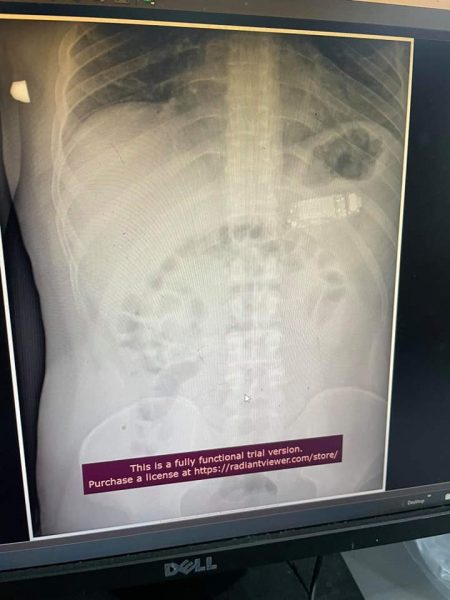

Një ndërhyrje e pazakontë është realizuar ditën e djeshme në Kosovë. Një 33-vjeçarit i është hequr nga barku telefoni, pasi katër ditë më parë e kishte gëlltitur atë.

Doktor Telaku tha se fillimisht nga barku i 33-vjeçarit u nxorën kapakët e telefonit e më pas bateria, kjo e fundit konsiderohet më e rrezikshmja.

“Ata më thirrën për një rast, ishte një person që kishte gëlltit një trup të huaj, u desht të bëhet gastroskopia me urgjencë, kur hynëm në lukth e pam që ishte telefoni i ndarë në pjesë tri pjesë. Një pjesë ishte kapaku i përparshëm dhe i pasmi i plastikës, plus bateria brenda. Hyjmë me pajiset që i kemi këtu, njëherë e nxorëm një pjesë, mandej pjesën tjetër, në fund e nxorëm edhe baterinë, nga të gjitha këto pjesë bateria është më e rrezikshmja sepse ajo pjesë ishte ajur dhe mund të shpërthejë. Mund të lëshojë materie kimike dhe mund t’i shpërthejë zorrët”, tha Teleku për Gazetën Express.

Pamje të telefonit që qëndroi katër ditë në stomakun e pacientit ka publikuar doktor Skender Telaku.

“Mashkulli 33 vjec para 4 ditesh kishte perbire nje telefon te vogel. Me rruge endoskopike, pra pa e prere lukthin, nxorrem telefonin e ndare ne tri pjese. Pa komplikime”, ka shkruar ai.